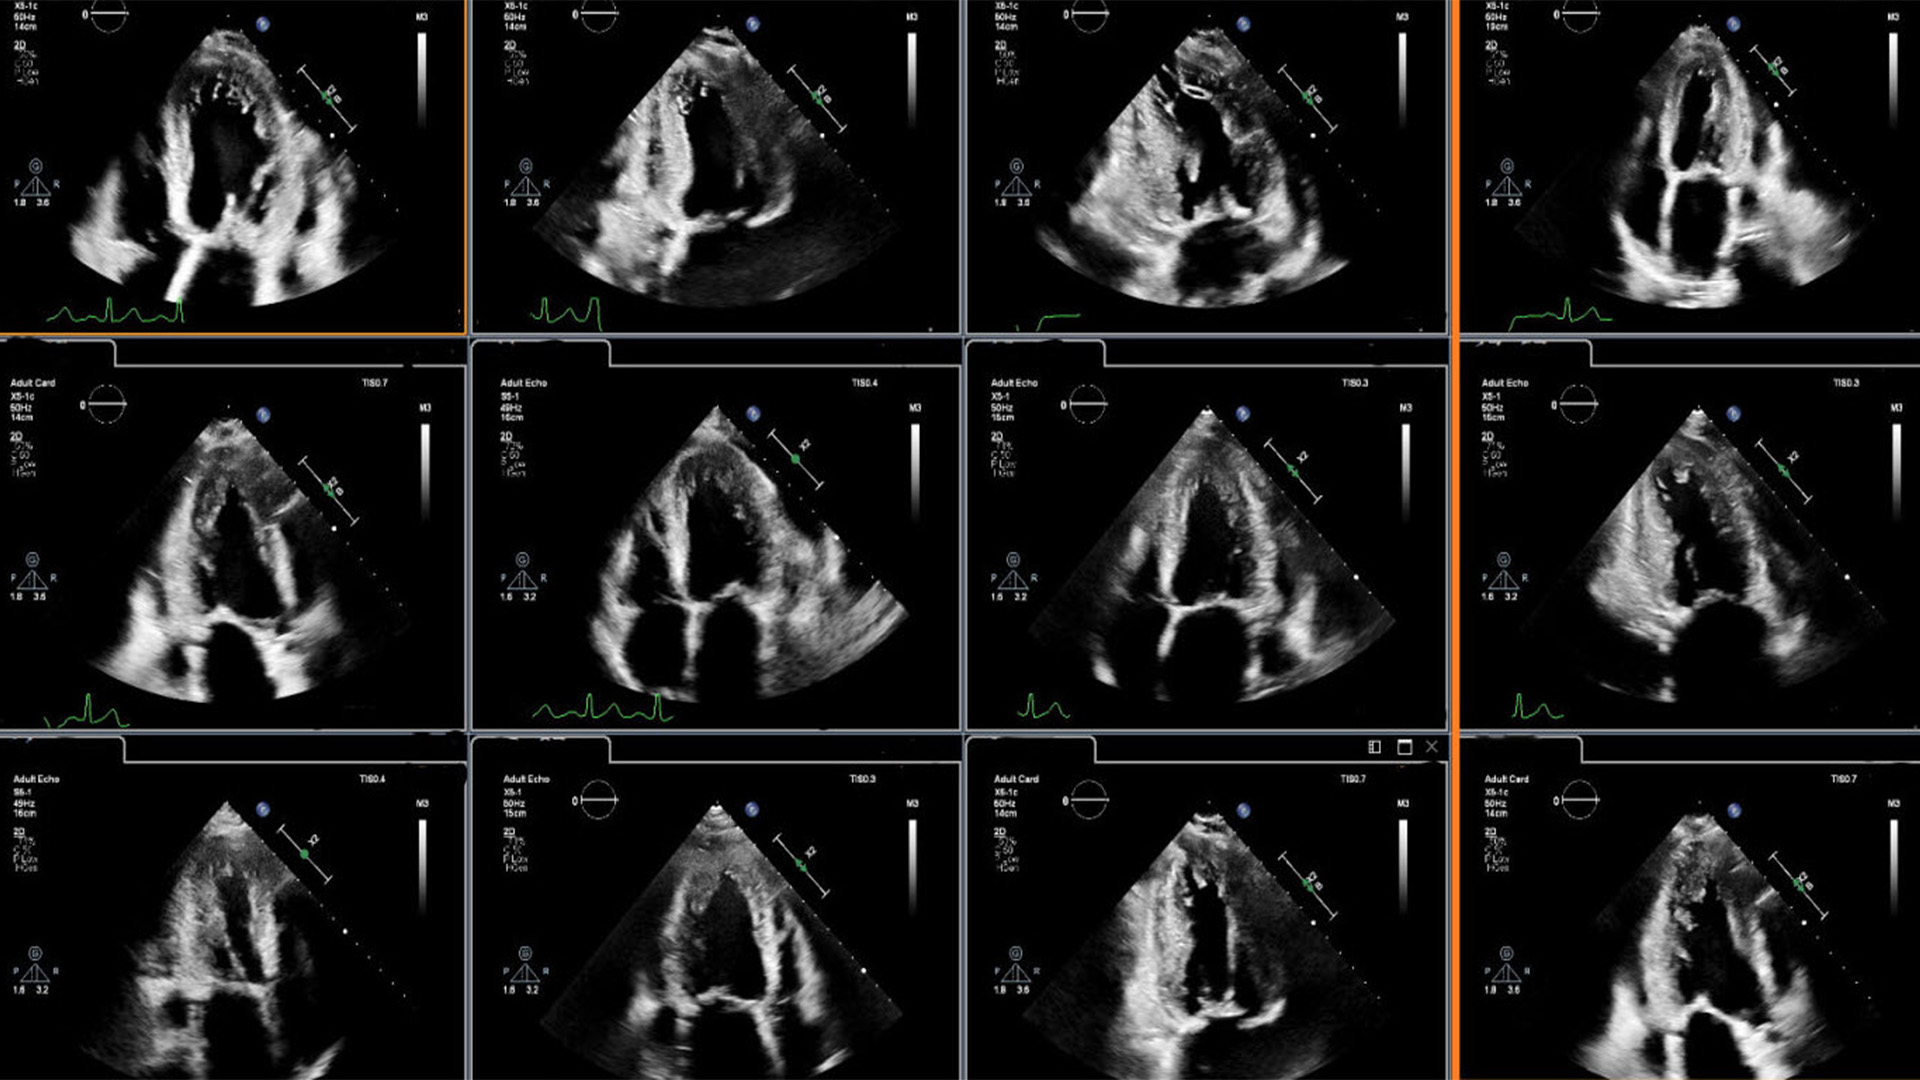

Dr. Lang heeft samen met andere artsen nieuwe inzichten gepresenteerd tijdens de jaarlijkse bijeenkomst van de American Society of Echocardiography (ASE2024) die van 14 t/m 16 juni plaatsvindt in Portland, VS. Hierin wordt uitgelegd hoe in samenwerking met Philips ontwikkelde AI-algoritmen op zeer nauwkeurige wijze regional wall motion abnormalities (RWMA) kunnen detecteren. RWMA's kunnen een indicator zijn van cardiovasculaire voorvallen en overlijden bij patiënten met hart- en vaatziekten, zoals een hartinfarct (myocardial infarction) en aangeboren hartaandoeningen. Geautomatiseerde, op machine learning gebaseerde beoordeling van RWMA’s heeft de potentie om cardiologen en echolaboranten verder te ondersteunen en efficiënter te werken verbeteren. "Een voordeel van AI ten opzichte van conventionele visuele analyse is dat deze binnen enkele seconden kunnen worden uitgevoerd, waardoor snelle en nauwkeurige informatie wordt verkregen; de analyse door deskundigen wordt verbeterd doordat zorgelijke RWMA's snel worden geïdentificeerd, waardoor de interpretatie eenvoudiger en efficiënter wordt," vertelt Lang.

De AI-functies die in de cardiovasculaire echografiesystemen van Philips zijn opgenomen, zijn getraind met behulp van geanonimiseerde patiëntgegevenssets uit de klinische praktijk en helpen de kwaliteit en reproduceerbaarheid van de beeldvorming van het hart te verbeteren en de efficiëntie van gebruikers en afdelingen te verhogen. Deze omvatten door de FDA goedgekeurde en CE-gemarkeerde softwareoplossingen van DiA Imaging Analysis, een Philips-bedrijf. Samen automatiseren deze AI-functies de manier waarop gebruikers echografiebeelden interpreteren, waardoor gebruikers met verschillende niveaus van echografie-ervaring sneller, efficiënter en nauwkeuriger in real time beelden kunnen analyseren.